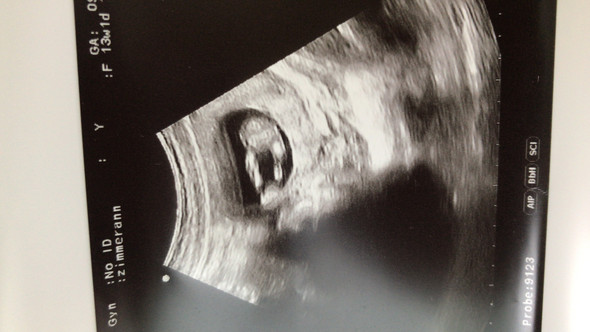

Ultraschallbild Madchen Oder Junge Schwanger Wer Noch

Was Meint Ihr Was Es Wird Schwangerschaft Ultraschallbild

Ultraschallbild Eher Madchen Oder Eher Junge Schwangerschaft

Madchen Oder Junge Was Seht Ihr Auf Dem Ultraschallbild

Ultraschallbild Madchen Oder Junge Liebe Und Beziehung